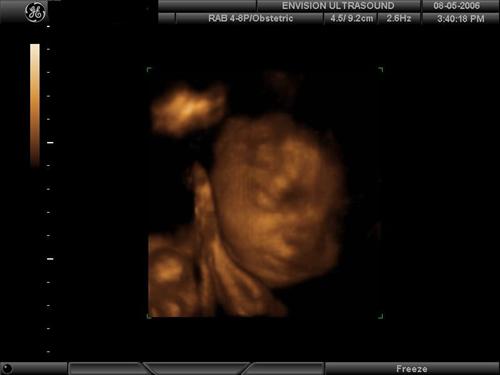

Ok you guys asked for it  We went to Envision Ultrasound in Brooklyn, per the recommendations of so many ladies on this board. I had checked with my doctor and she totally approved us having this done. If anyone has any questions and /or would like more details about Envision, I would be happy to give you my insight into the experience.. they were wonderful. Here are some of my favorite pics of our little monkey ... Favorite face shots:

a little smirky/smile

He started smooshing his FOOT right up against his face.. very flexible little guy

This pic cracks me up…holding his foot up with his fists